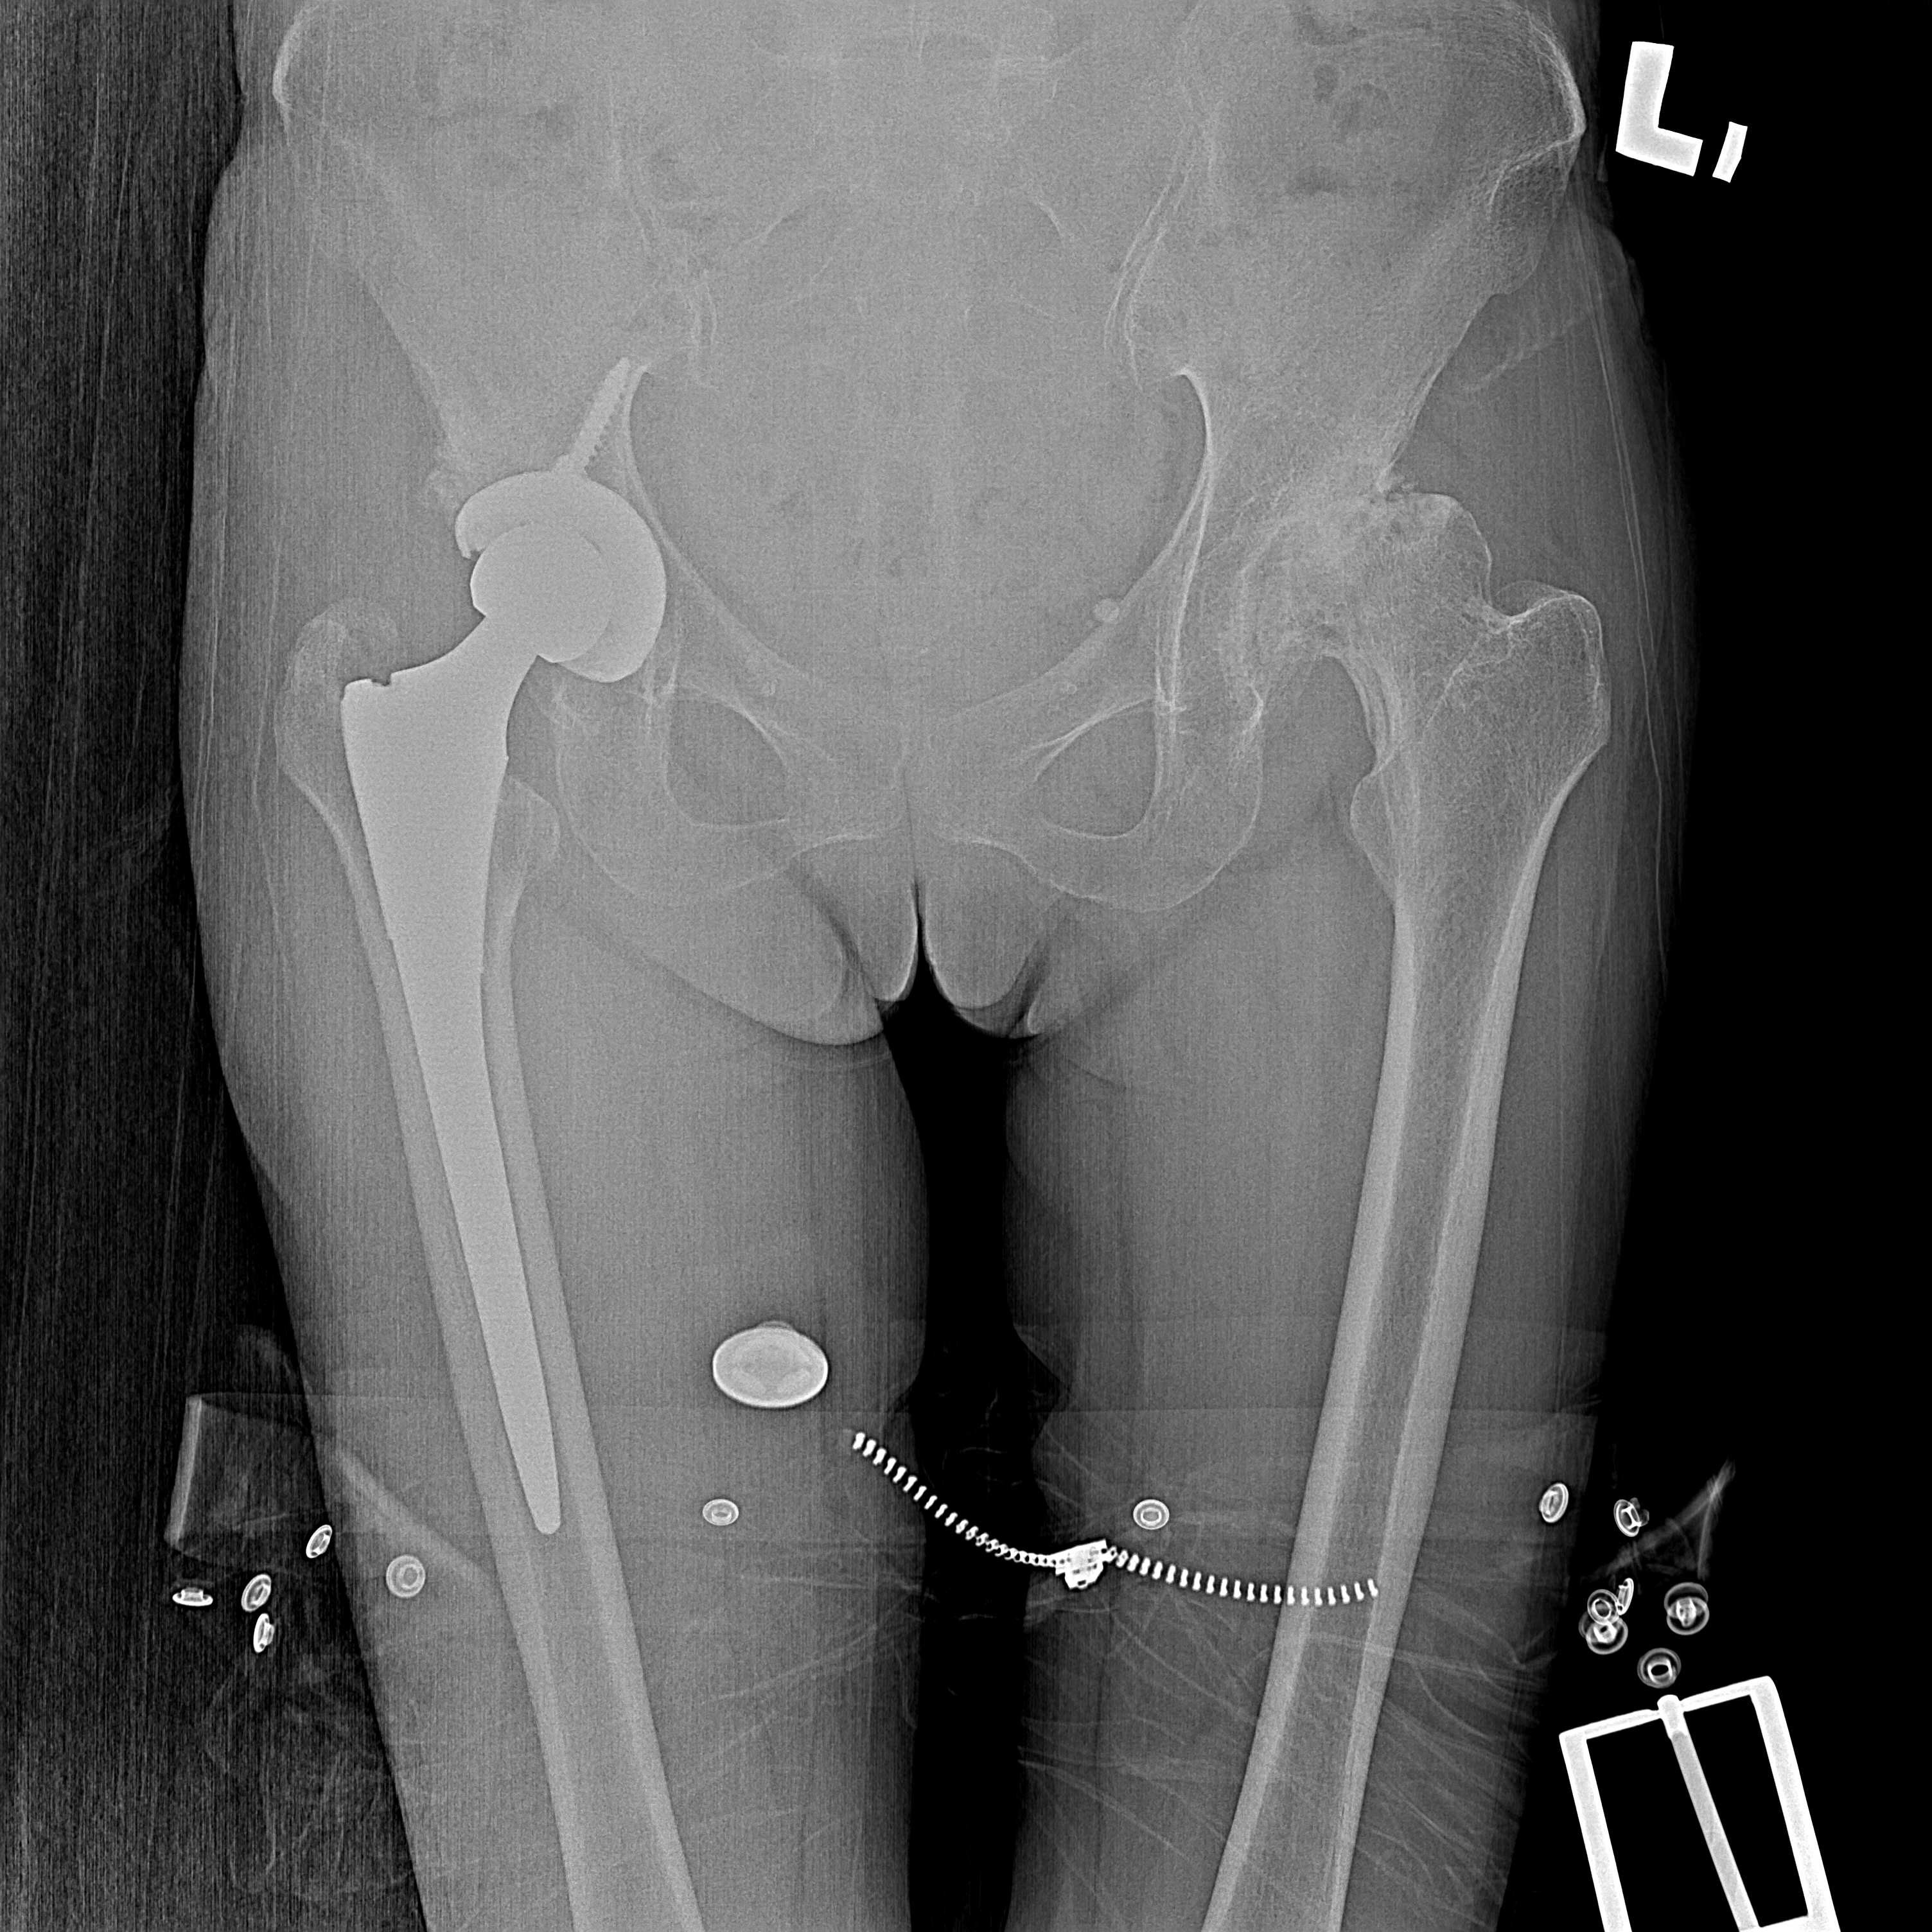

傳統髖關節置換 首頁 案例分享 髖關節手術 傳統髖關節置換 54歲蔡先生退化性關節炎 術前 術後 張女士 51歲 退化性關節炎(DDH先天發育不全 CROWE TYPE 2) 術前 術後 38歲林先生 退化性關節炎 術前 術後 72歲謝女士 退化性關節炎 術前 術後 71歲 謬女士 骨股頭壞死 術前 術後 50歲 郭先生骨股頭壞死 術前 術後 80歲 盧先生骨股頭壞死 術前 術後 林先生 37歲 術前 術後 邱女士 51歲 術前 術後 張女士 50歲 術前 術後